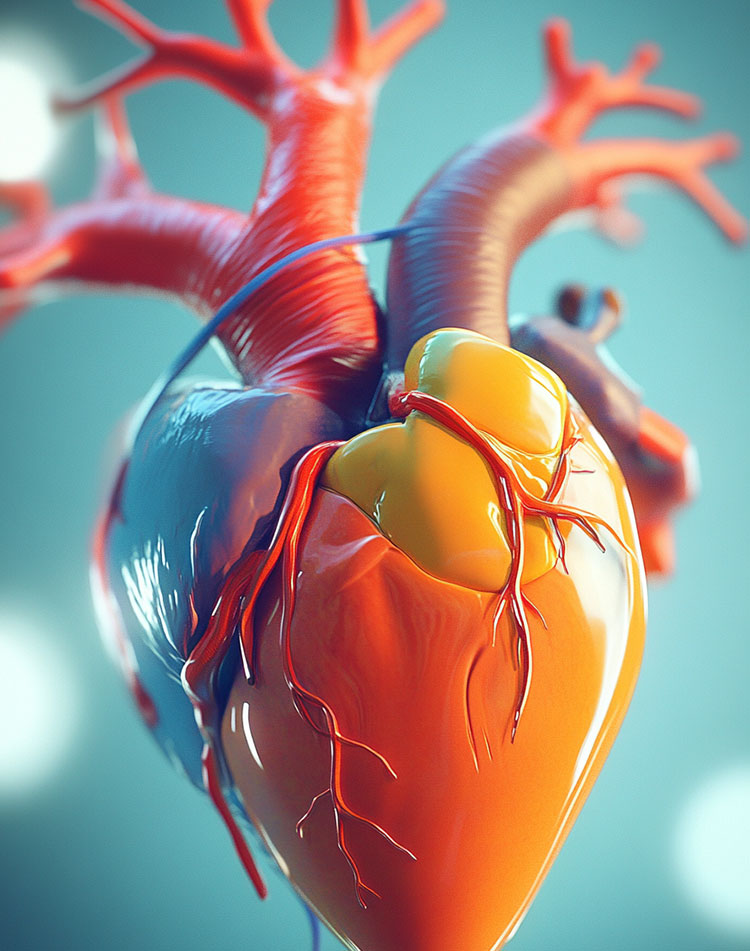

CollectiveX AI: Revolutionizing Medical Diagnosis and Treatment Planning

Discover how CollectiveX's AI-powered platform is enhancing diagnostic accuracy and treatment planning. By combining global medical expertise with advanced artificial intelligence, we're improving patient outcomes and revolutionizing healthcare delivery.